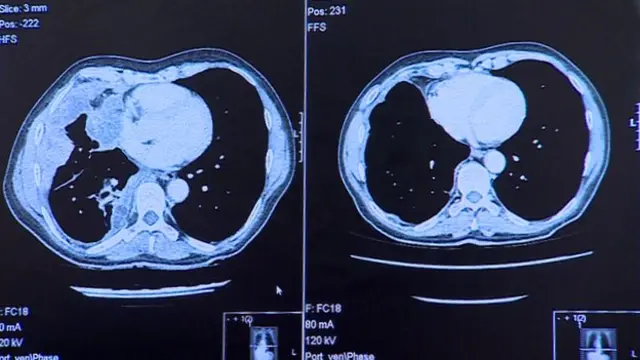

وتظهر الأشعة التي أجريت على رئتيه أن العلاج تمكن بعد ثلاثة جرعات فقط من تطهير الرئة تماما من السرطان.